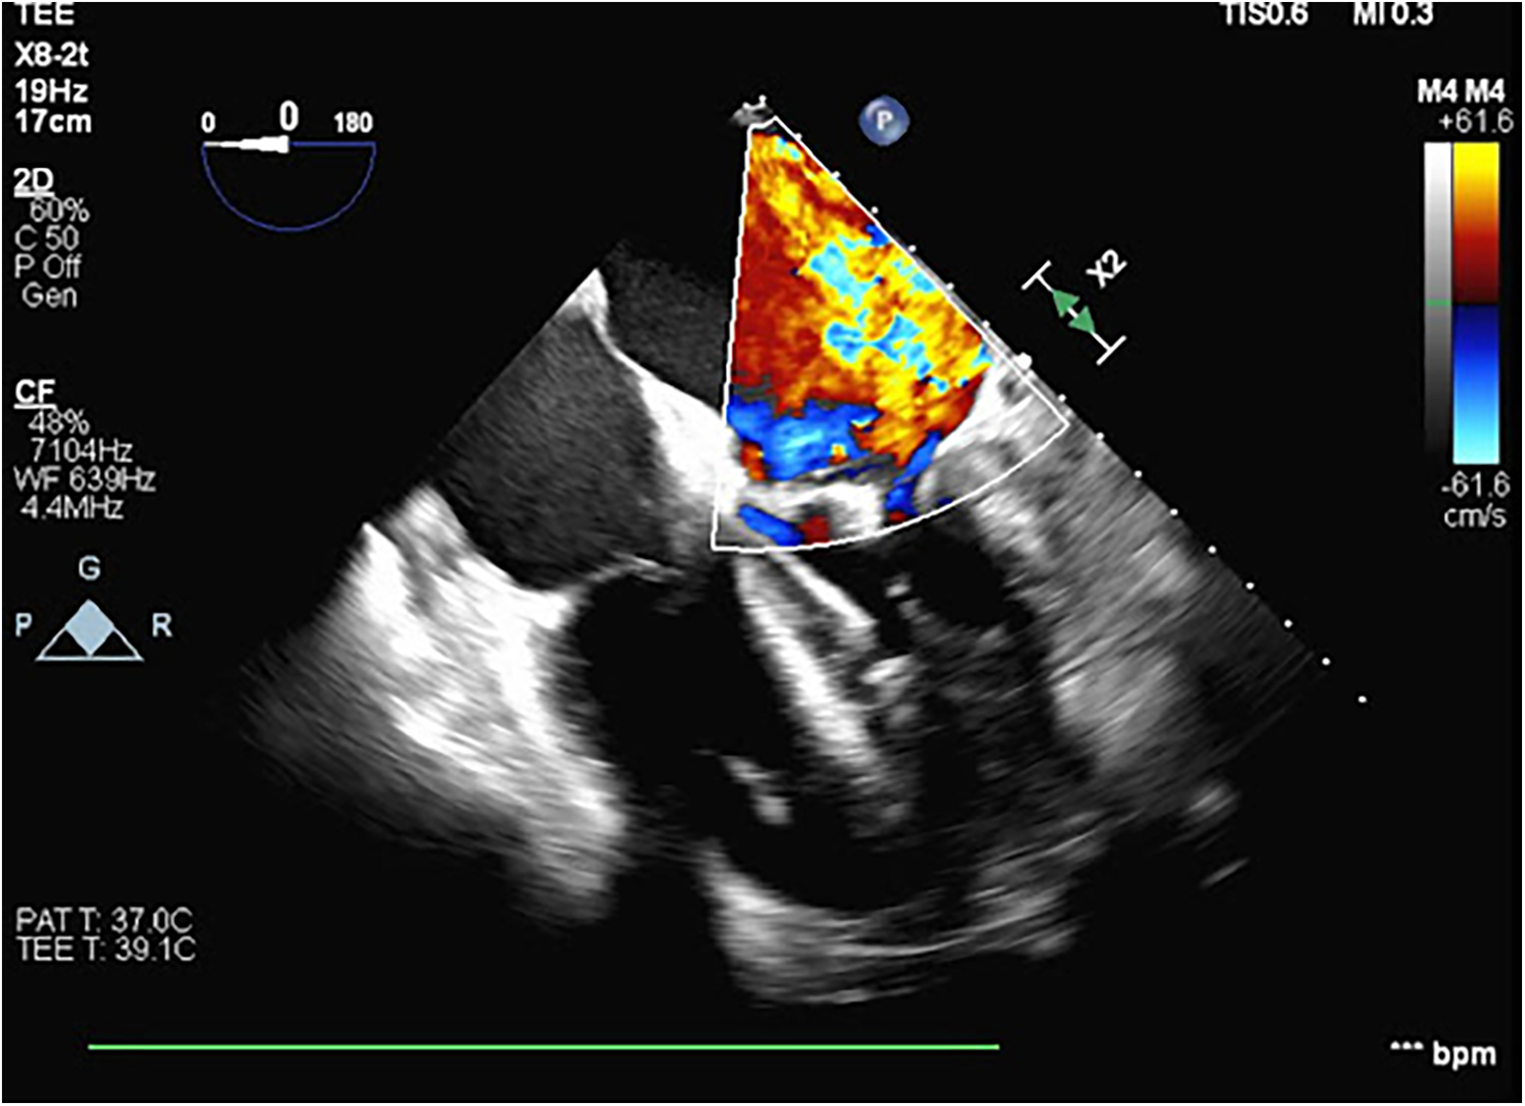

Figure 2

A transesophageal echocardiogram performed during VA ECMO cannulation and Impella placement showing severe mitral regurgitation with the central jet and a thickening of the mitral valve leaflets.

The patient was taken emergently to the operating room for an initiation of VA ECMO and placement of an Impella® device (Abiomed, Inc., Danvers, MA, USA). Right heart catheterization revealed a pulmonary capillary wedge pressure of 50 mmHg and a right atrial pressure of 20 mmHg. The pulmonary artery oxygen saturation rate was noted to be 36% as measured using a Swan-Ganz catheter. Femoral cannulation ensued with flows of 5.4l and an Impella-assisted cardiac output of 4 LPM. A transesophageal echocardiogram was obtained at the time of ECMO cannulation, demonstrating severe mitral regurgitation with the central jet filling the left atrium. The patient was taken to the cardiac intensive care unit for hemodynamic stabilization and preoperative optimization. While in the ICU[AQ: Please define “ICU” at first occurrence.], metabolic acidosis was corrected, overall volume status improved with diuresis, reaching a negative volume balance of 6 L, and hemodynamics stabilized.